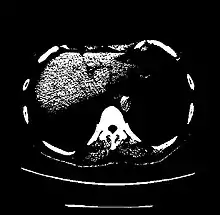

| Liver | 60 ± 6[23] | |

A practical application of this is in evaluation of tumors, where, for example, an adrenal tumor with a radiodensity of less than 10 HU is rather fatty in composition and almost certainly a benign adrenal adenoma.[28]